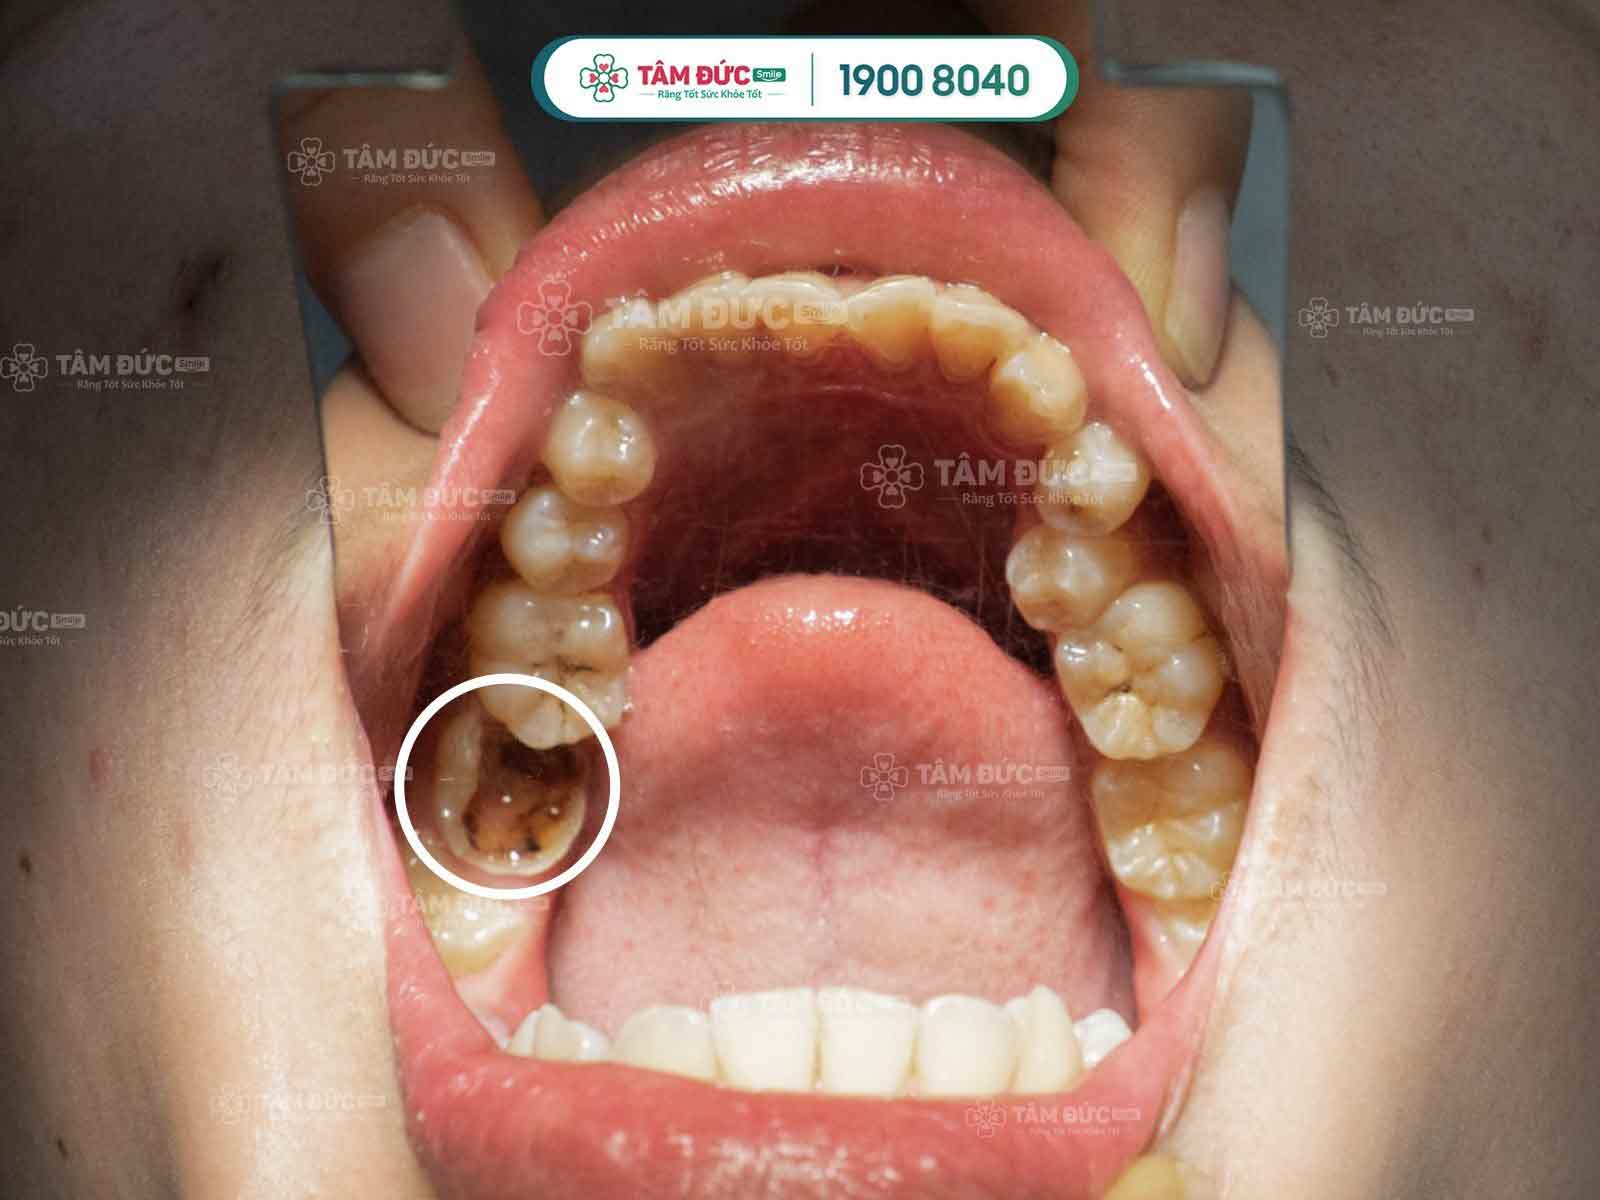

Thường nguyên nhân chính dẫn đến viêm tủy là sâu răng, các mảng bám từ thức ăn lâu ngày không được vệ sinh sẽ hình thành vôi răng, trong vôi răng đó chứa rất nhiều vi khuẩn có khả năng phá hủy, ăn mòn răng của Quý khách xuất hiện tình trạng răng xuất hiện các lỗ đen. Và kéo dài tình trạng này lâu, vi khuẩn sẽ ăn mòn lớp răng vào đến tủy, gây viêm tủy.

Các bệnh nhân sâu ăn vào đến tủy thường sẽ cảm thấy đau nhức răng, ăn nhai khó khăn, ảnh hưởng xấu đến sức khỏe.

- Răng bị mẻ, vỡ lớn, sâu răng làm lộ tủy gây viêm tủy, nhiễm trùng.